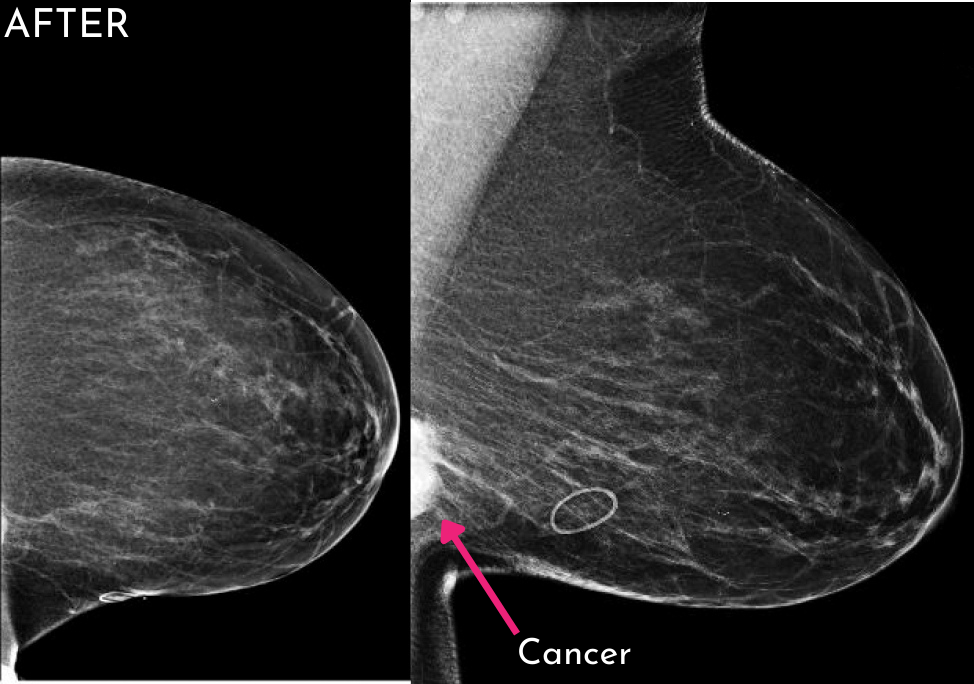

When comparing “before” and “after” images, the improvement can often be startling, even if the original images were really good! We have even identified cancers that were not visualized the year prior. Now that is amazing!

While no change can guarantee you will avoid regulatory scrutiny, proactive improvements absolutely strengthen image quality, especially when it comes to positioning. Research published in the American Journal of Roentgenology (1) supports this. According to the U.S. Food and Drug Administration, poor positioning reduces the sensitivity of mammography by 18.1%. That means we miss more early cancers when positioning is not optimal. That number alone should be the motivation for change and the desire to be proactive in your approach to providing the highest quality care for our patients